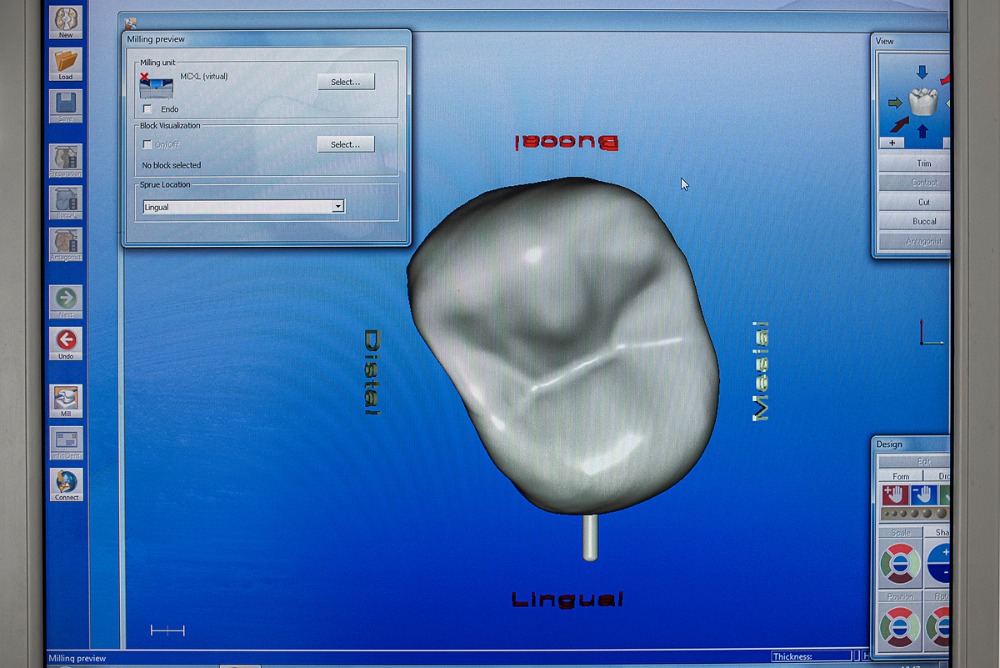

Výroba estetických celokeramických korunek dle sceneru, individuálně pro každého jednotlivého pacienta, dle vzhledu, fyziognomie obličeje a genetiky zubů.